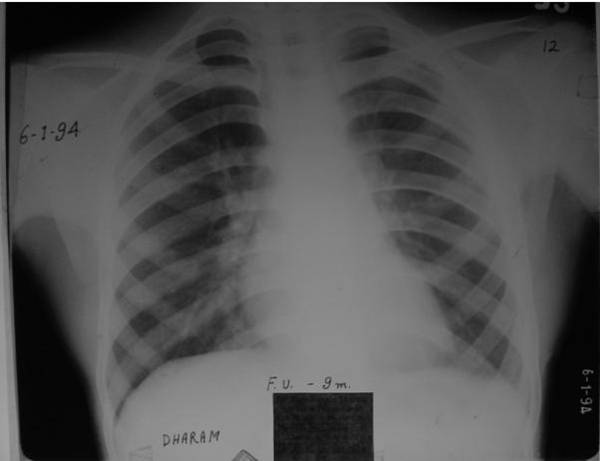

Dated: 6 Jan. 1994.

Again there is a process of resolution of fibrosed pleura is visible.